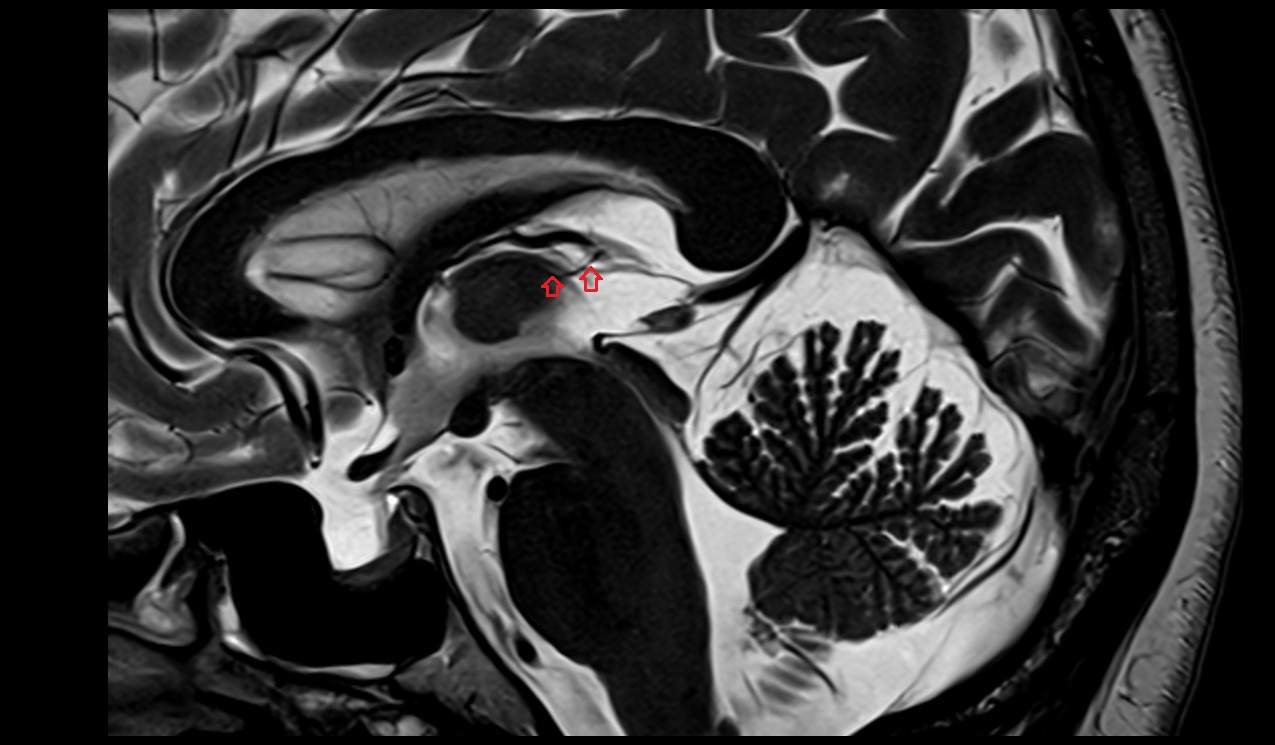

- Fetal brain

- Fetal caudate nucleus

- Fetal thalamus

- Fetal pons

- Fetal cerebellum

- Fetal third ventricle

- Fetal fourth ventricle

- Fetal lateral ventricle